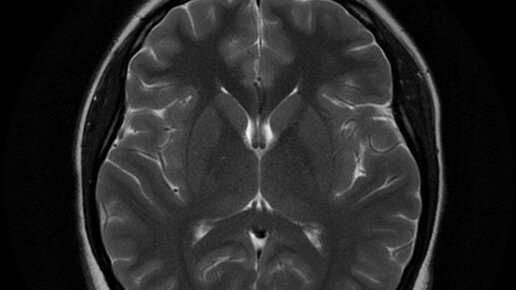

Чем отличается МРТ от КТ головного мозга и что лучше?

Когда в процессе поиска причин плохого самочувствия мы задаемся вопросом, что лучше - МРТ или КТ головного мозга для диагностики, Правильный ответ сразу неочевиден, поскольку оба этих метода скорее дополняют, чем соперничают друг с другом...

КТ или МРТ — что лучше? Разбираем, когда и какое исследование нужно

Врач назначил томографию, а в голове сразу возникает вопрос: что выбрать — КТ или МРТ? Может, это одно и то же, только названия разные? Или у одного «магия», а у другого «техника»? Давайте разбираться спокойно и по существу, ведь правильная диагностика — это половина успеха на пути к выздоровлению. «Лучше знать, чем гадать» — этот принцип в медицине работает на 100%. Или проще: КТ — это «рентген в 3D», а МРТ — «магнитное зрение» вглубь организма. Всё зависит от цели исследования. Вот несколько примеров: Тогда первое, что стоит сделать — обратиться к врачу...

КТ или МРТ: что лучше пройти?

Снимки, полученные во время КТ и МРТ, очень похожи, – но только на первый взгляд. На самом деле это очень разные диагностические методики, и у каждой есть свои показания. Фундаментальное отличие в том, что во время компьютерной томографии для исследования тела человека используют рентгеновские лучи, а во время магнитно-резонансной томографии – сильное магнитное поле. В каждом конкретном случае выбирают не то, что больше нравится пациенту или доктору, а то, что лучше поможет решить конкретную диагностическую задачу...